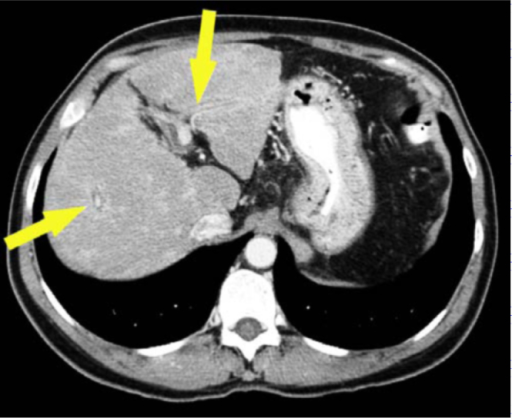

Open-I Concentric Rings: Updated CT Appearance of Hepatic Schistosomiasis Mansoni. Lee D, Shaffer K - Radiology case reports (2015)

| actual | 12:51 2 may 2020 | 512 × 418 (190 kB) | Rossdonaldson1 (discusión | contribs.) | Open-I Concentric Rings: Updated CT Appearance of Hepatic Schistosomiasis Mansoni. Lee D, Shaffer K - Radiology case reports (2015) |